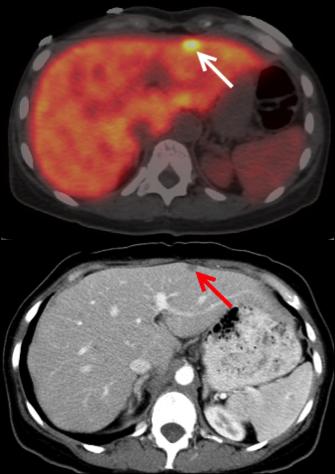

A pet scan is often done in combination with a ct scan. It's difficult to see or feel pancreatic tumors because the pancreas is so. Pancreatic cancer — overview covers symptoms, risk factors, prevention, diagnosis, surgery, chemotherapy and other treatment for cancer of several types of growths can occur in the pancreas, including cancerous and noncancerous tumors. If you have jaundice and suspected pancreatic cancer, or if you have been diagnosed with pancreatic cancer that is contained within the pancreas (localised pancreatic cancer) after a ct scan, you should also. A special type of ct known as a multiphase ct scan or pancreatic.

Ct scanning will visualize the vast majority of pancreatic cancers, and it provides important information to guide treatment. A special type of ct known as a multiphase ct scan or pancreatic. Effectiveness of ct scan for pancreatic cancer detection. A pet scan is often done in combination with a ct scan. A computerised tomography (ct) scan is a commonly used test to assess pancreatic cancer. Why aren't pancreatic ct scans used in routine physical examinations to detect and prevent the spread of pancreatic cancer? This depends on the reason for your ct scan and which part of your body your doctor needs to see. Pancreatic cancer (cancer of the pancreas) mainly occurs in people aged over 60.

First line investigations ct scan for the scanner is shaped like a doughnut. Computed tomography (ct or cat) scan. Multidetector ct scanning (mdct) using a pancreas protocol is at least as accurate as eus in the overall determination of the resectability of pancreatic algorithm for evaluation of a patient with suspected pancreatic cancer. The ct scans, four of them over the course of the 11 weeks from my initial appointment with my primary (23 march). An abdominal ct scan is an imaging method. If you have jaundice and suspected pancreatic cancer, or if you have been diagnosed with pancreatic cancer that is contained within the pancreas (localised pancreatic cancer) after a ct scan, you should also. Pet/ct fusion scan enhances ct staging in patients with pancreatic. Home about pancreatic cancer diagnosis of pancreatic cancer how is pancreatic cancer diagnosed? It is about three feet wide and is open at both ends. For evaluating possible pancreatic cancer, a multiphase helical ct scan or pancreatic protocol ct scan is often recommended. Effectiveness of ct scan for pancreatic cancer detection. Hongwei li1, kanru lin3, maximilian reichert2, lina xu1, rickmer braren2 1 introduction. Learn how this test works, as well as its benefits and risks.

Ct stands for computed tomography. The ct scans, four of them over the course of the 11 weeks from my initial appointment with my primary (23 march). Many cancer centers use a special ct scan method called a pancreatic protocol ct scan. Pancreatic cancer — overview covers symptoms, risk factors, prevention, diagnosis, surgery, chemotherapy and other treatment for cancer of several types of growths can occur in the pancreas, including cancerous and noncancerous tumors. But if a needle biopsy is needed, most doctors prefer to use it might be especially useful for spotting cancer that has spread beyond the pancreas and wouldn't be treatable by surgery. Ct scans are often performed to monitor patients after treatment to determine whether the cancer has recurred, changed in size or metastasized this test is not as specific as ct scanning and is not used alone to diagnose pancreatic cancer. Pancreatic cancer will typically refer to ductal carcinoma of the pancreas, which comprises up to 90% of primary pancreatic malignancies. This provides a series of images from many different angles.